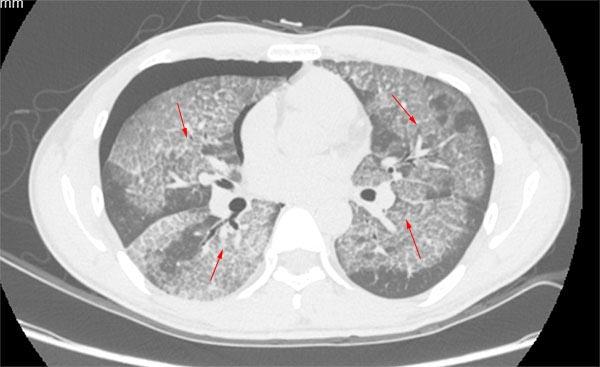

【呼吸科】全肺灌洗术是治疗肺泡蛋白沉积,尘肺矽肺的

ct2940:胸部,尘肺乎.粟粒样肺结核乎.迷茫.

尘肺的影像表现及鉴别诊断

尘肺病ct影象图片

尘肺的ct图片

二期尘肺图 尘肺病

二期尘肺图 40万

二期矽肺ct图片特征

尘肺二期ct报告单图片